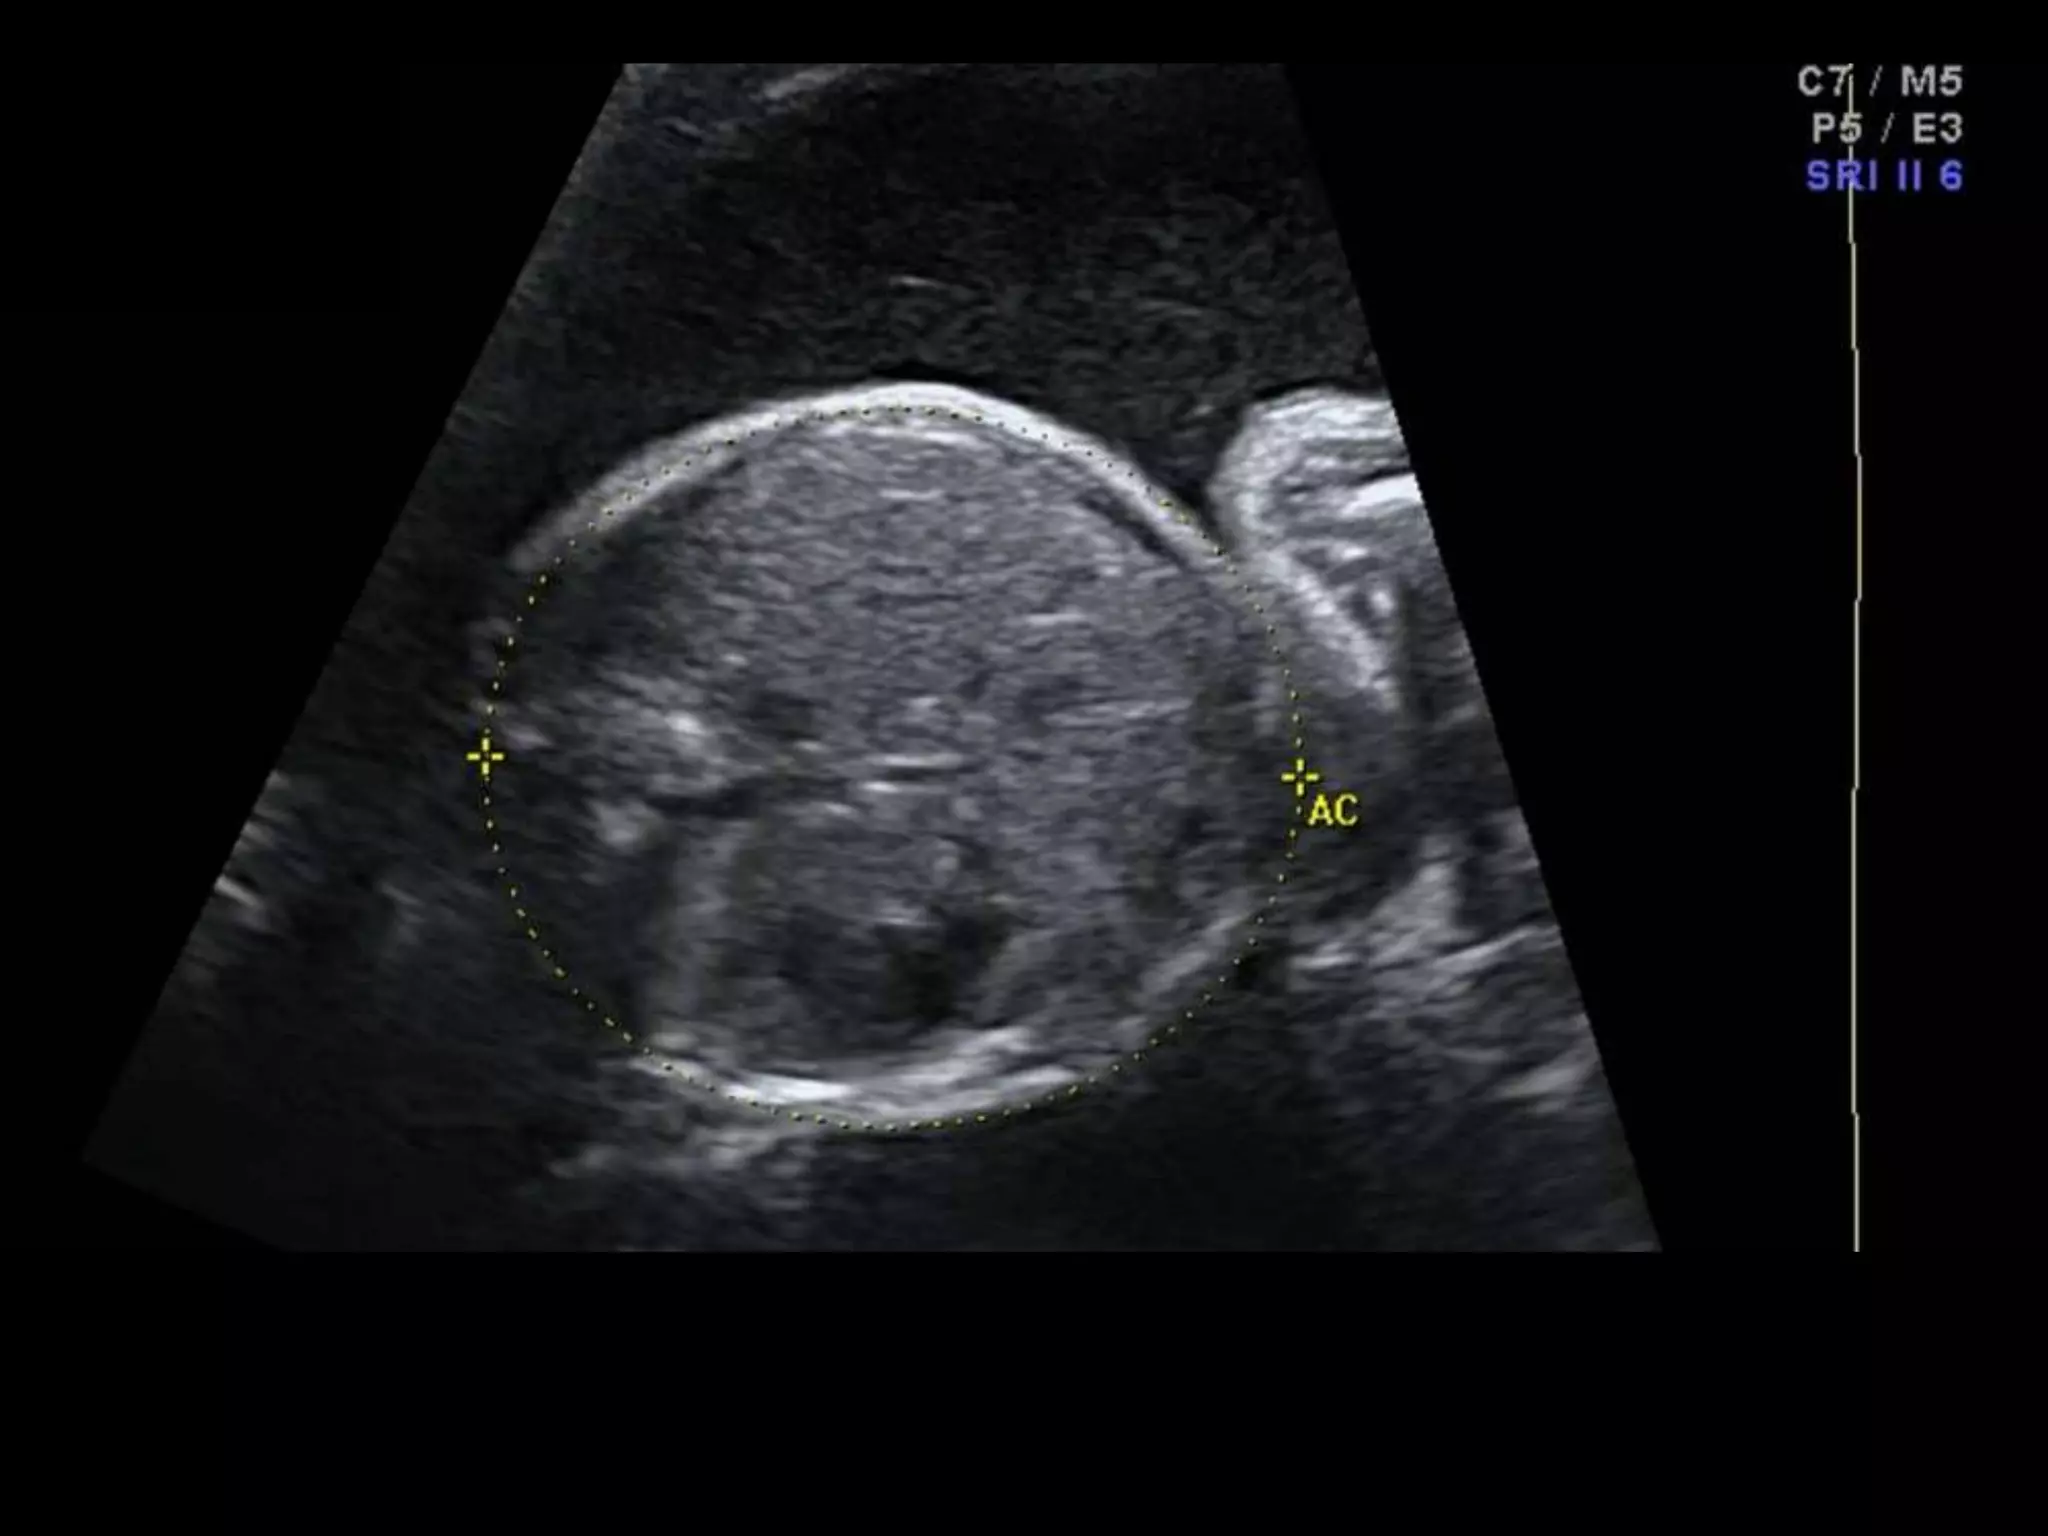

โ€ข 36 yo female 30.5 weeks pregnant

โ€ข Referred with โ€žmultiple fetal anomaliesโ€Ÿ for

fetal ultrasound

LUS โ€“ Cephalic

HISTORY โ€ข 36 yofemale 30.5 weeks pregnant โ€ข Referred with โ€žmultiple fetal anomaliesโ€Ÿ for fetal ultrasound